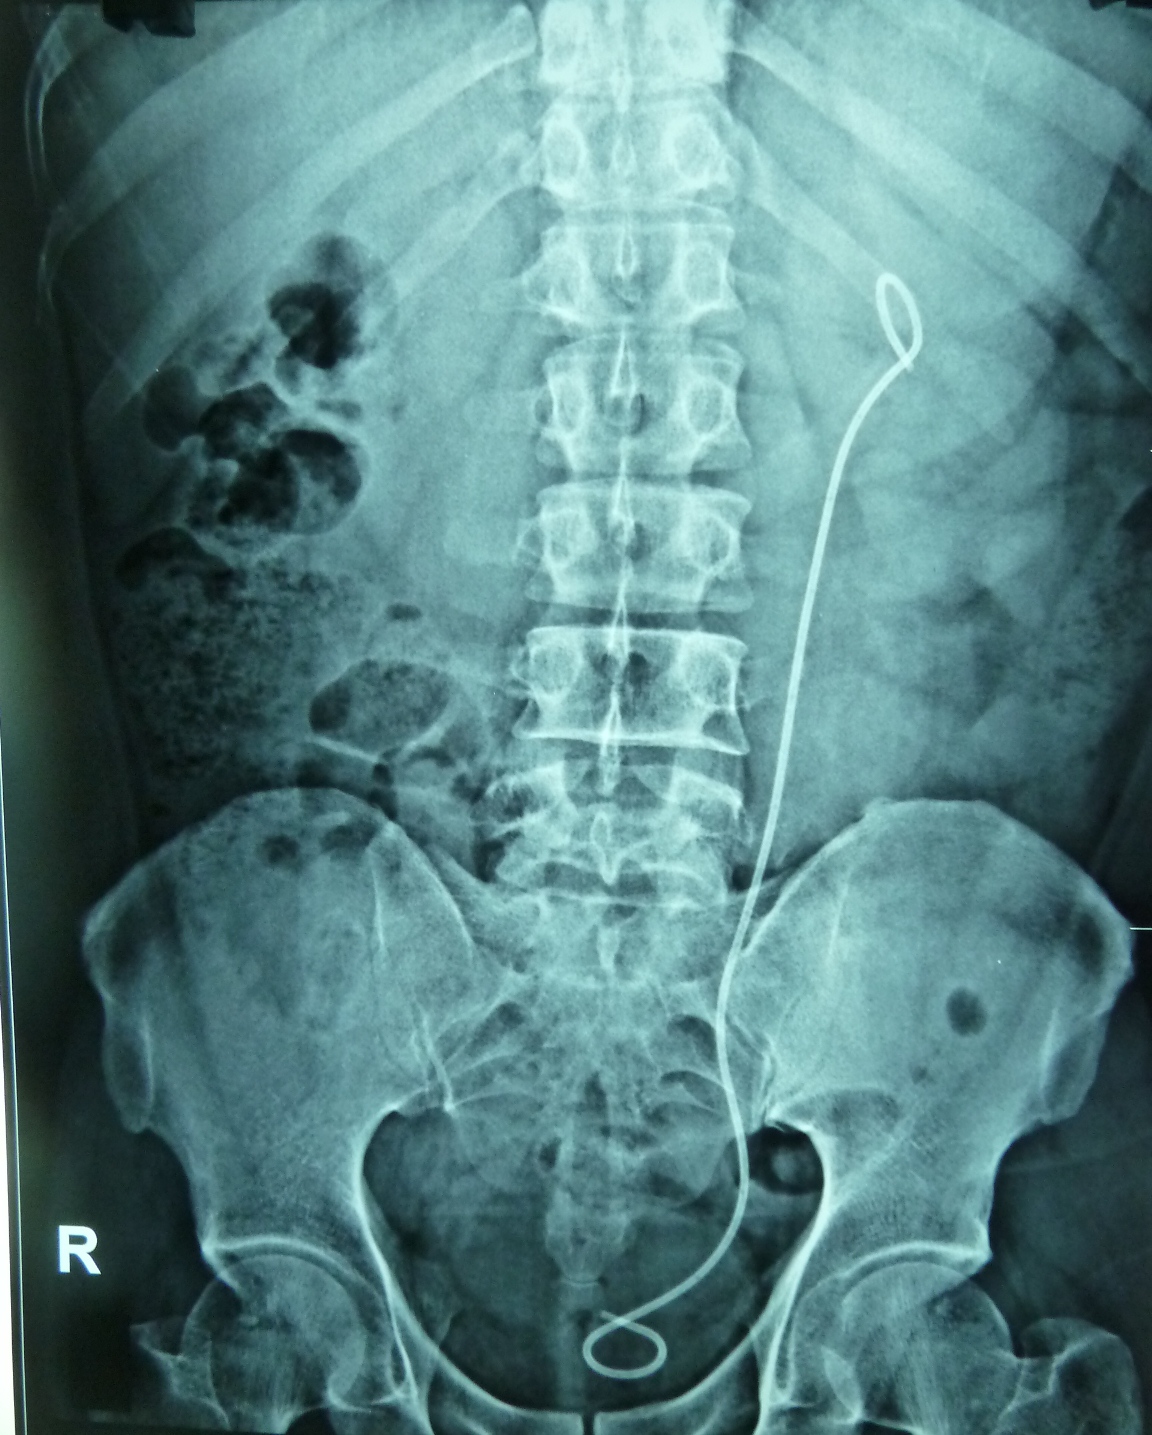

From drramayyas.blogspot.com

Ramayya Pramila Urology Hospital Partial staghorn kidney stone removed What Is A Partial Kidney Removal Called Most often, it's done to treat kidney cancer or to remove a tumor that isn't. nephrectomy is the partial or complete removal of a kidney. It allows you to retain some kidney function. The goal is to remove the diseased or. Bilateral nephrectomy is the surgical removal of both kidneys. partial nephrectomy is used to treat kidney cancer. What Is A Partial Kidney Removal Called.